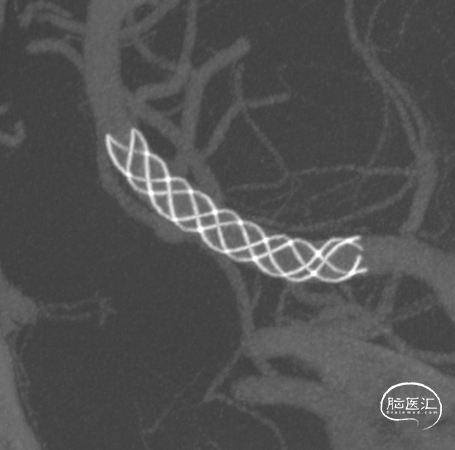

Vaso CT显示 畅医达(Choydar)血流导向装置 位置良好,完全覆盖瘤颈,长轴及横轴薄层均显示支架贴壁良好。

支架部分释放后复查造影示支架位置良好,缓慢完全释放支架,支架打开良好,复查造影示支架位置良好,完全覆盖瘤颈,贴壁佳,瘤囊内可见造影剂滞留明显,OKM分级A3。

畅医达(Choydar)3mm以下血流导向装置可经其小外径0.017微导管输送系统释放,通过性好,支架推送及释放过程平顺,径向支撑力高,支架打开贴壁良好,对于Willis环以远的远端动脉瘤治疗到位率及成功率高,头端封闭结构减少对血管壁的损伤,安全性好。